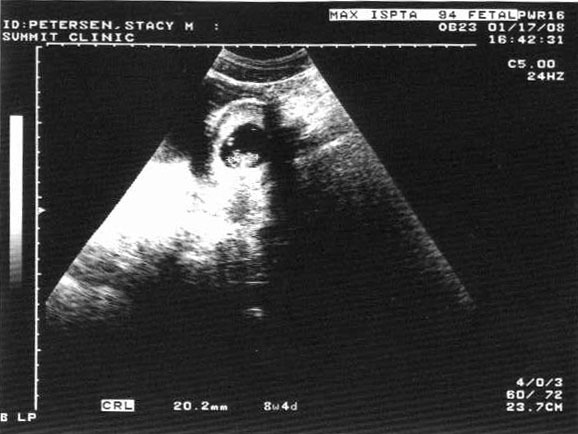

So grateful for Pizza Monday! 2 miles on the treadmill and 2 pieces of pizza. And I think to myself, "What a wonderful world." Okay, it's decision time. Moab is about four weeks away and I have done a total of 6 walking miles in 2 weeks. I'm not going to run Moab. I'm still going to Moab and I'm definitely still getting my shirt and hat (I didn't pay $50 for a 5 mile race not to get any souvenirs). It's just that, while everybody else is getting up early and standing in the cold and running a race, I'll be sleeping in and eating ginger pancakes with apple butter at the Jailhouse Cafe. I'm really trying to see the downside of this decision. I'm pretty disappointed in myself, but I think it's the right thing to do. If I had gotten pregnant one month earlier, I probably would have had enough time to recover from the first trimester fatigue a little and at least walk the 5 miler, but I drag my feet doing 2 miles on the treadmill right now and I don't see it getting anywhere near 5 in the next month. So, disappointing, yes, but at least there are pancakes to be had. |